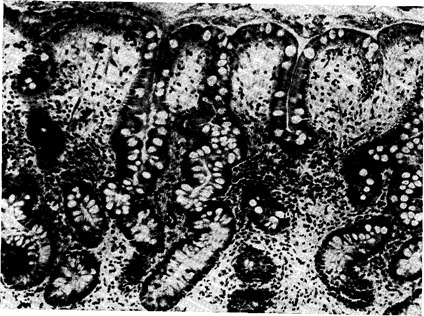

Рис. 61. Поверхностный гастрит (увеличение в 150 раз). Мелкоклеточная инфильтрация интсрстипиума, преимущественно в слое ямок и в попер хнр-.тном железистом слое слизистой. (Биопсия, микрофотография проф. Беднаржа.1)